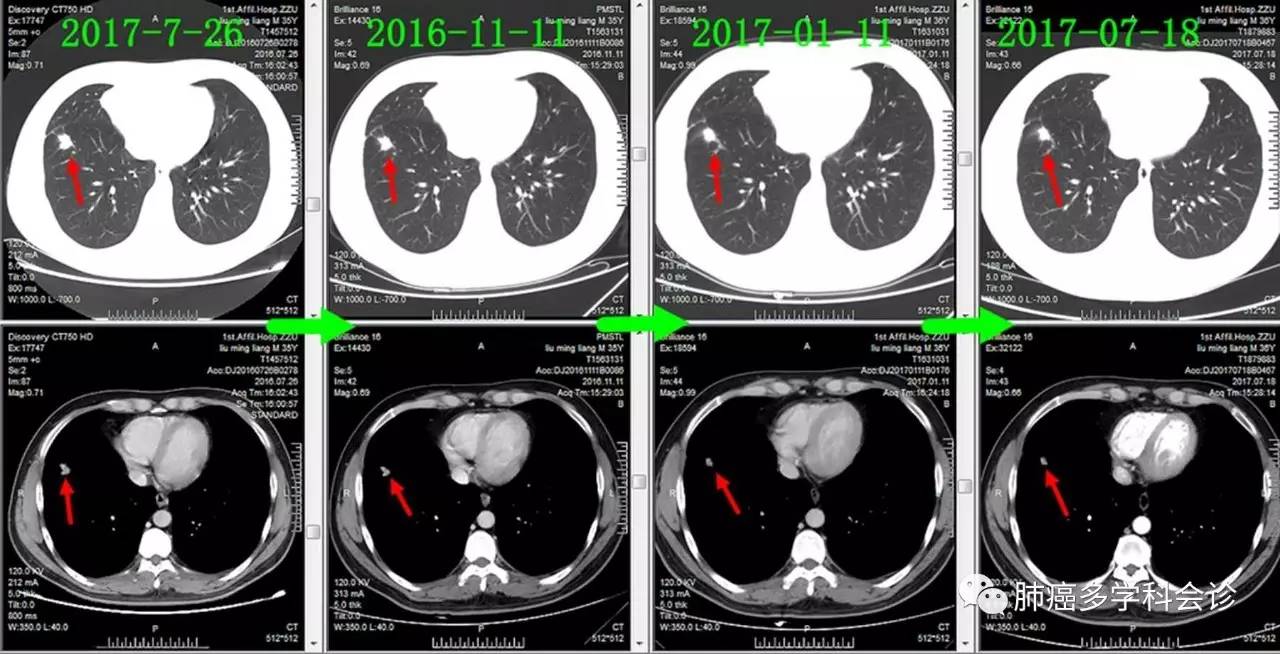

下面通过对比治疗过程中胸部CT变化,展现胸部肿瘤此消彼长的过程:

肺原发灶略有缩小

纵隔肿大淋巴结逐渐缩小

胸膜转移灶消失

食管转移灶从小到大